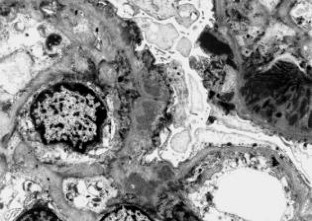

Die Lupusnephritis ist ein bekanntes Phänomen beim systemischen Lupus erythematodes (SLE). Wir untersuchten die Nierenbiopsie einer 30-jährigen Frau mit SLE. Die Anamnese zeigte einen klinisch typischen SLE mit generalisierten Symptomen mit positivem ANA- und Anti-ds-DNA-Titer ohne Nachweis von Lupuskoagulans, des Rheumafaktors, von Kryoglobulinen sowie ohne Antiphospholipid-Antikörper. Eine Paraproteinämie war weder für IgG noch für IgA oder IgM nachzuweisen. Mit Hilfe der Lichtmikroskopie, der Elektronenmikroskopie sowie der Immunelektronenmikroskopie wurden elektronendichte Ablagerungen in subepithelialer, subendothelialer und mesangialer Lokalisation nachgewiesen. Zusätzlich fanden wir sowohl in den elektronendichten Ablagerungen, als auch im angrenzenden Mesangium Kristalle eines elektronendichten Materials. Diese kristallinen Strukturen sind aus IgG und κ-Leichtketten zusammengesetzt, während IgM, IgA sowie λ-Leichtketten mittels Immunelektronenmikroskopie nicht nachzuweisen waren.

Lupus nephritis is a common phenomenon in Systemic Lupus Erythematosus (SLE). We analyzed a renal biopsy of a 30-year-old woman with SLE. The clinical history showed a typical SLE with generalized symptoms without demonstrable lupus coagulant, positive for anti-nuclear antibodies and anti-ds-DNA antibodies but negative for rheumatoid factor, cryoglobulins and antiphospholipid antibodies. A paraproteinemia for IgA, IgG and IgM was not detectable. Using light, electron and immunoelectron microscopy electron-dense deposits were noted in subepithelial, subendothelial and mesangial position. Most remarkably, the electron-dense deposits and mesangial areas in the vicinity of deposits contained an electron-dense crystalline material. The crystalline structures were composed of IgG and kappa light chains, while they were negative for IgM, IgA and lambda light chains, as demonstrated by immunoelectron microscopy.

Abb. 2.